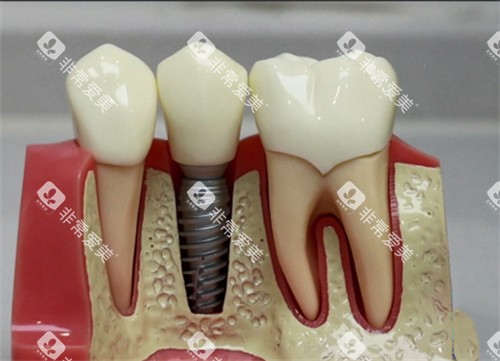

方案1:种植牙——牙槽骨的"定海神针"

"这是目前比较接近真牙的修复方式。"李医师指着种植体模型,"把纯钛'人工牙根'种进牙槽骨,3-6个月骨结合后装牙冠。"他强调:"但骨量萎缩超过50%就做不了,得先植骨。"